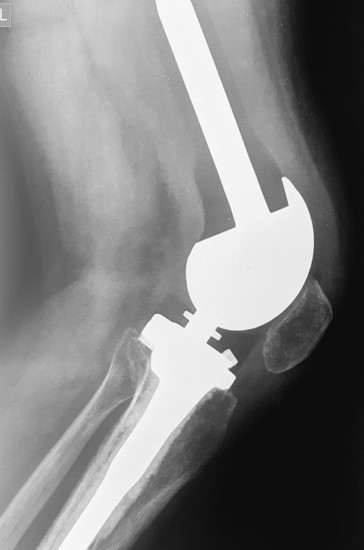

2. Բժշկական տարբեր կենտրոններում հետազոտվելուց հետո՝ 17-ամյա պատանին դիմել է «Նաիրի» ԲԿ։ Համապատասխան հետազոտություններ անցնելուց հետո՝ բուժառուի մոտ հայտնաբերվել է ոլոքի օստեոսարկոմա (ոսկրային քաղցկեղ): Նախավիրահատական բուժում ՝ քիմիոթերապիա, ստանալուց հետո՝ «Նաիրի» ԲԿ ում կատարվել է օրգանապահպան վիրահատություն : Հեռացվել են ծնկահոդն ու ոլոքի վերին երորդականը: Առաջացած դեֆորմացիան շտկել է Եվրոպայից պատվիրված էդոպրոթեզով, որը հնարավորություն է տվել պահպանել վերջույթի գործառույթը՝ քայլել, վազել և այլն։ Հետվիրահատական շրջանում բուժառուն ստացել է քիմիոթերապիա։ Այժմ գտնվում է բժիշկների հսկողության ներքո։

Վիրահատությունից առաջ

Վիրահատությունից հետո